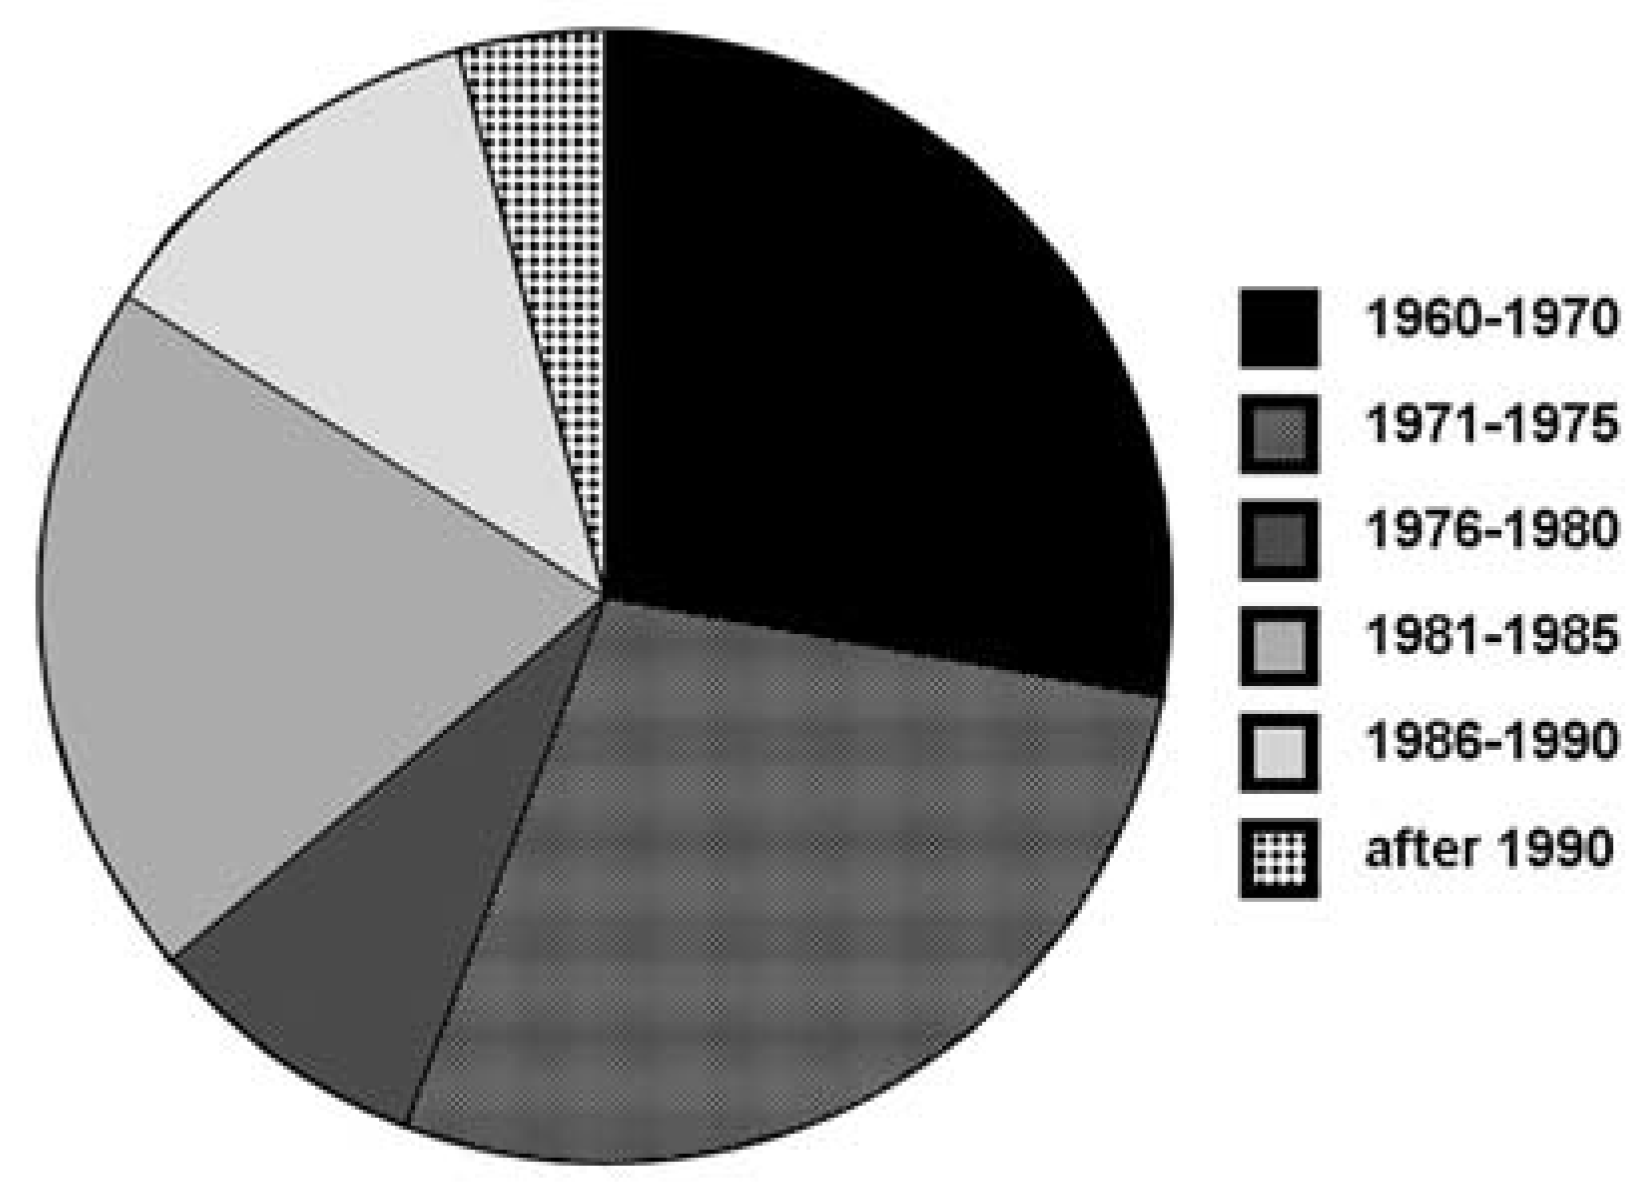

|